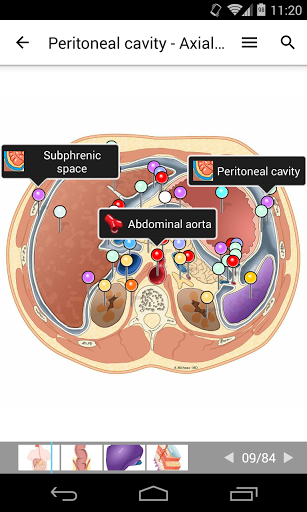

-The pins mode have a new behaviour allowing you to follow an anatomical structure much more easily

-Within the details view of an anatomical structure, a pin now points the related structure in all present images

Also tap directly on the image to navigate to the presented image in that module